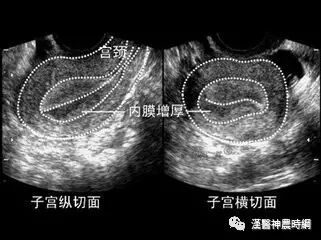

增厚的原因

内源性雌激素

1、不排卵:在青春期女孩、围绝经妇女、下丘脑-垂体-卵巢轴的某个环节失调、多囊卵巢综合征等,都可有不排卵现象,使子宫内膜较长期地持续性受雌激素作用,无孕激素对抗,缺少周期性分泌期的转化,长期处于增生的状态。40 岁以下子宫内膜不典型增生患者中,其内膜除了有灶性不典型增生以外,其他内膜80%以上无分泌期;基础体温测定结果70%为单相型。故大多数患者无排卵。

2、肥胖:在肥胖妇女,肾上腺分泌的雄烯二酮,经脂肪组织内芳香化酶作用而转化为雌酮;脂肪组织越多,转化能力越强,血浆中雌酮水平越高,因而造成持续性雌激素的影响。3、内分泌功能性肿瘤:内分泌功能性肿瘤是罕见的肿瘤,但在研究统计中属内分泌功能性肿瘤的占7.5%。垂体腺的促性腺功能不正常,卵巢颗粒细胞瘤也是持续性分泌雌激素的肿瘤.